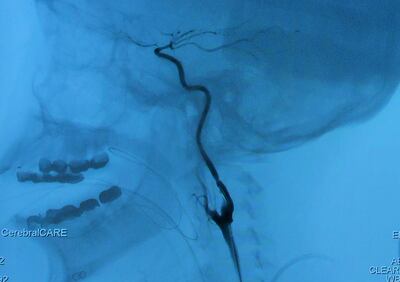

A battery of tests found she had moyamoya disease, a rare condition first identified in Japan. The name means "puff of smoke," and describes patients' X-rays, which show a cloud of fragile blood vessels that sprout in the brain where normal vessels are blocked.

Her recent operation was the first bypass Langer performed with the Orbeye, though he and his colleagues had used it for other operations. This type of bypass is one of the most difficult neurosurgical operations, and requires stitching together arteries that are only a millimetre or so in diameter. Colleagues say Langer is one of the few surgeons in the world with the skill and experience to perform it well.

The procedure started with assistant surgeons touching an ultrasound probe to Roy’s temple to detect the pulse of the scalp artery, and then marking the vessel’s path with purple ink so that Langer would know precisely where to cut. Then he would begin the painstaking process of freeing the two branches of the artery from their surrounding tissue.

When the scalp artery was free, the surgeons took a drill and a saw to Roy’s skull, removing a disc of bone about three inches in diameter. Magnified 15 times on the monitor, her brain, webbed with bright red blood vessels, gleamed in the light and pulsated with each heartbeat.

It took about 10 stitches to sew the scalp artery to the artery in the brain, using a curved needle about the size of an eyelash and fine thread barely visible to the naked eye.

When the stitching was done, Langer used an ultrasound probe to check for the rhythmic whooshing sound that would mean blood was flowing through the newly created channel.

Initially, the flow was weak, and another neurosurgeon, eyeing the monitor, suggested a bit more dissection to loosen the recipient artery. Langer took his advice. It worked.